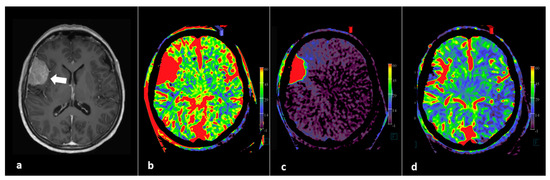

- Fujimoto, M.; Itokawa, H.; Moriya, M.; Okamoto, N.; Sasanuma, J. Evaluation of Cerebral Hyperperfusion After Carotid Artery Stenting Using C-Arm CT Measurements of Cerebral Blood Volume. Clin. Neuroradiol. 2018, 28, 253–260. [Google Scholar] [CrossRef]

- van der Zijden, T.; Mondelaers, A.; Voormolen, M.; Yperzeele, L.; Menovsky, T. Vessel territory mapping after cerebral revascularization surgery using selective angiographic flat detector perfusion imaging. J. Integr. Neurosci. 2021, 20, 103–107. [Google Scholar] [CrossRef] [PubMed]